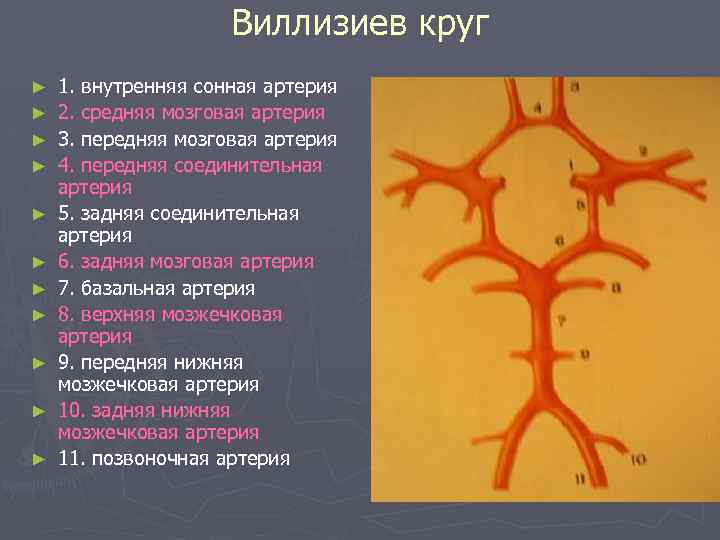

Виллизиев круг ► ► ► 1. внутренняя сонная артерия 2. средняя мозговая артерия 3. передняя мозговая артерия 4. передняя соединительная артерия 5. задняя соединительная артерия 6. задняя мозговая артерия 7. базальная артерия 8. верхняя мозжечковая артерия 9. передняя нижняя мозжечковая артерия 10. задняя нижняя мозжечковая артерия 11. позвоночная артерия